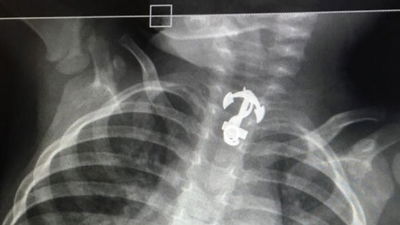

בדיקת הרנטגן לפעוט בן השנתיים הותירה את הצוות הרפואי המום לנוכח החפץ הגדול שנמצא בוושטו של הפעוט שהובהל מיידית לבית החולים כדי לשחרר מגרונו את התליון (בריאות)